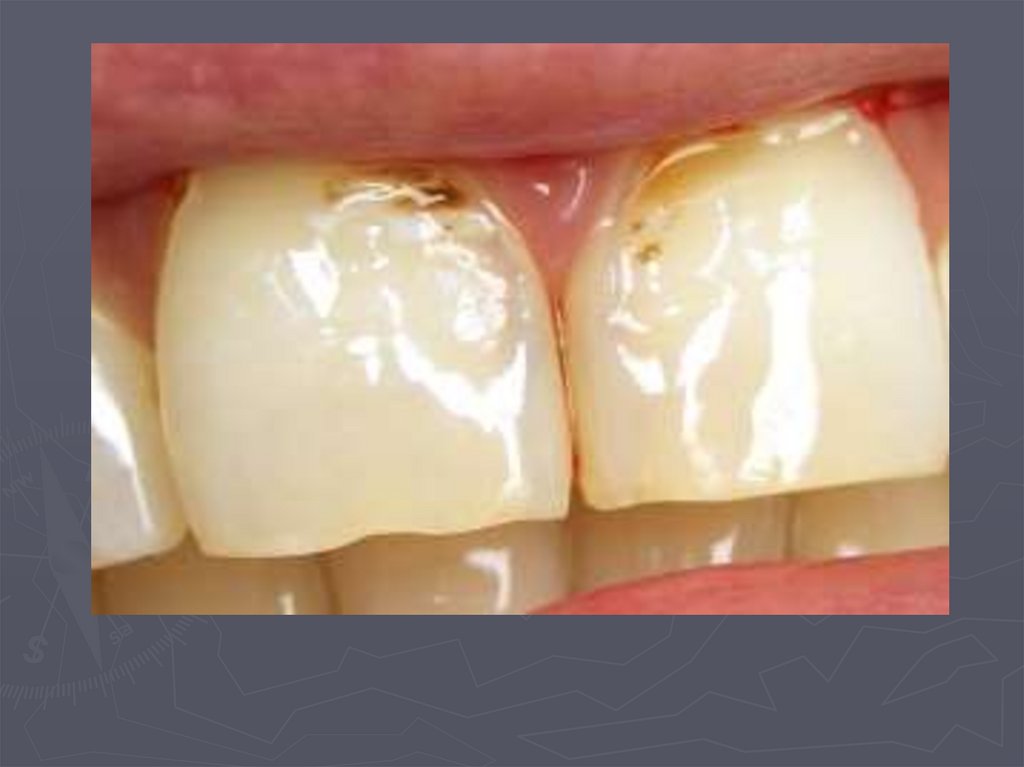

21. Начальный кариес (кариес в стадии пятна)

22. Начальный кариес (кариес в стадии пятна)

23. Начальный кариес (кариес в стадии пятна)

25. Начальный кариес (кариес в стадии пятна)

26. Начальный кариес (кариес в стадии пятна)

27. Начальный кариес (кариес в стадии пятна)

19. КЛИНИЧЕСКАЯ КАРТИНА НАЧАЛЬНОГО КАРИЕСА при компенсированной форме:

► заболевание протекает бессимптомно;

► участок поражения может быть покрыт зубным

налетом;

► в участке поражения пятно меловидное или

пигментированное;

► эмаль пятна матовая;

► поверхность пятна гладкая, плотная;

► зондирование безболезненно;

► на температурные раздражители не реагирует.

20. КЛИНИЧЕСКАЯ КАРТИНА НАЧАЛЬНОГО КАРИЕСА при декомпенсированной форме:

►пятно белого или светло-коричневого

цвета;

► пятно не имеет четких границ;

► эмаль пятна тусклая;

► поверхность пятна шероховатая ;

►при зондировании эмаль неплотная.